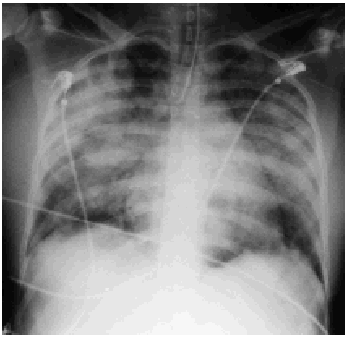

La evolución fue favorable y se pudo retirar el apoyo hemodinámico y respiratorio, aunque el destete se retrasó por la aparición de fiebre por sobreinfecciones nosocomiales. Se realizó tratamiento antibiótico controlando los episodios infecciosos. La función cardíaca se normalizó, con ecocardiogramas de control con mejoría progresiva. En el momento del alta la función sistólica era normal, sin dilatación de ventrículo izquierdo, con normalización de la presión arterial pulmonar, sin encontrarse vegetosis y con persistencia de ligera hipocinesia inferoapical.